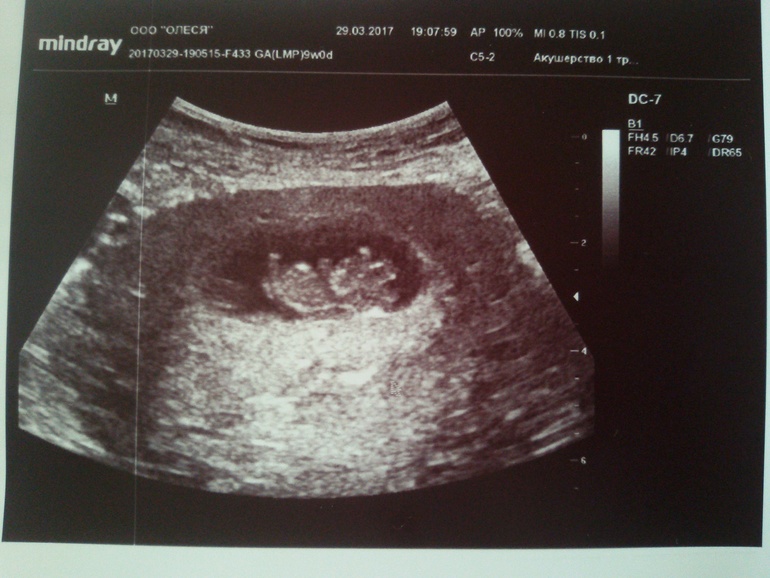

Наше четвертое УЗИ 😅😅😅

После прошлого УЗИ вынашивала мысль не ходить больше до скрининга, но в понедельник муж сказал "Как было бы хорошо сейчас малыша увидеть", ну и всё 😅 вся моя уверенность не идти на УЗИ куда-то улетучилась и пошли мы с мужем смотреть нашего Никитоса)) муж первый раз ходил, смотрел во все глаза и улыбался во весь рот с радостными возгласами "Он помахал мне ручками!! Он головкой покрутил!!" - радовался, как ребенок 😁

Итак, опережаем мы срок на 2-3 дня:) теперь ПДР ставят с 28 октября по 1 ноября) ну точно рожу на ДР старшей дочки (21.10))

Смотрели опять по животику, матка уже совсем поднялась, такими темпами скоро пузик начнет расти быстро, хоть малышастик маленький еще, всего 25 мм. С младшей дочкой в 15 недель уже такой пузяка большооой был, в 16 уже в бандаж влезла. В целом, всё отлично, как будто и не было никогда никаких чисток, выкидышей и т.д. Даже тонуса нет, прям очень радует всё.

Ну и наши фоточки и экспериментальный график БТ 😁

Вот так мы растем: